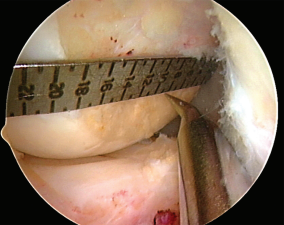

方法:221名医生在一具膝关节标本和一张有刻度的膝关节侧位X线片上表明了他们预期建立的股骨隧道的位置。然后每个外科医生在关节镜下手术演示定位股骨隧道的位置。这个位置是用术中C臂透视获取的。以股骨外侧髁的网格为参照,比较了预期建立和实际获得的隧道位置之间的欧几里德距离(两点之间的直线距离)。根据外科医生的观察入路(前内侧[AM]或前外侧[AL])、隧道定位策略(偏心定位器、解剖标志估计、ACL尺或C臂透视)和规定的钻孔技术(经胫骨钻股骨隧道、前内入路钻孔或由外向内钻孔)对数据进行分析。